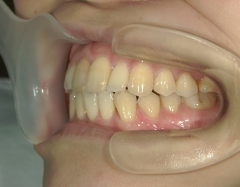

矯正歯科 治療後矯正歯科 プチワイヤー矯正 治療後矯正歯科(プチワイヤー矯正)治療後

矯正歯科 治療後  スペース確保の為、 2番抜歯

no.37_7548_治療後_右.JPGno.37_7548_治療後_正面.JPGno.37_7548_治療後_左.JPG